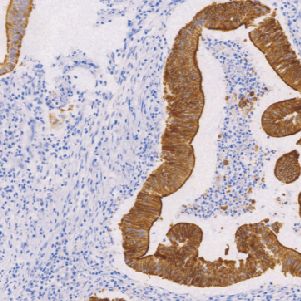

Villin鼠抗人绒毛蛋白单克隆抗体

Villin与结构相关蛋白凝溶胶蛋白(gelsolin)、片段化蛋白(fragmin)及割切蛋白(sevenrin),全部参与肌动蛋白(actin)的框架调节与装配正常分布于肠上皮和肾近小管上皮,可用于肠上皮来源肿瘤与非肠上皮肿瘤的鉴别诊断,亦可作为胃肠道神经内分泌肿瘤诊断参考指标。

- 阳性部位:胞质,胞膜

- 适用组织:石蜡切片

- 预处理:热修复